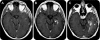

Objective: To examine the potential utility of conventional MRI signs in differentiating pseudoprogression (PsP) from early progression (EP).

Conclusions: Conventional MRI signs have limited utility in diagnosing PsP in patients with recently treated glioblastomas and worsening enhancing lesions. We did not find a sign with a high negative predictive value for PsP that would have been the most useful for the clinical physician. When present, subependymal spread of the enhancing lesion is a useful MRI marker in identifying EP rather than PsP.